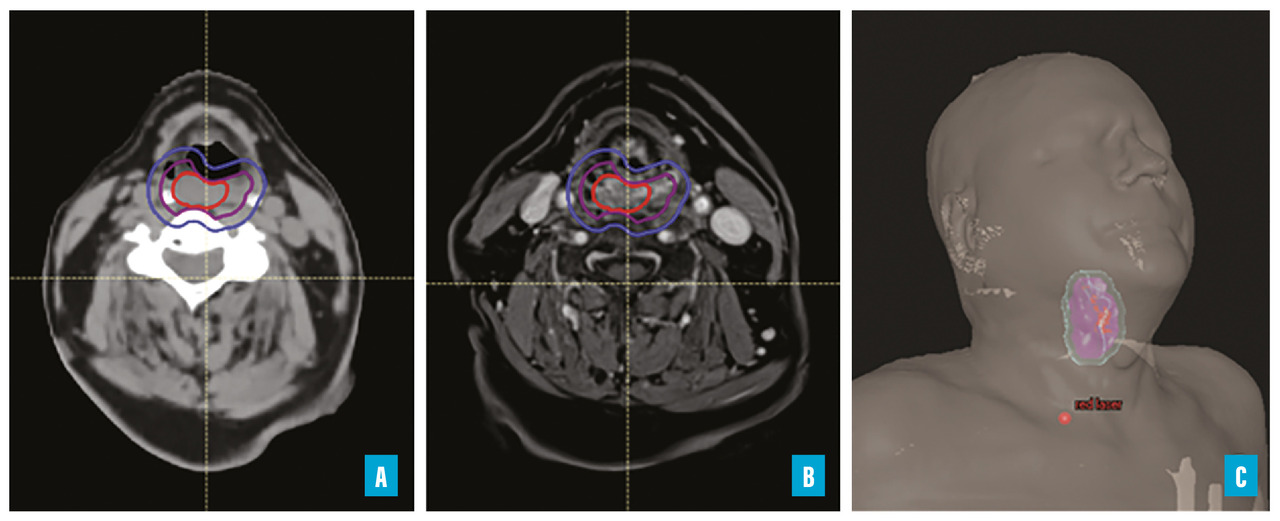

Après le scanner de positionnement, l’oncologue-radiothérapeute prend en charge le dossier pour ­délimiter les volumes cibles et les organes à risque (OAR). Selon les directives de l’International Commission on Radiation Units and Measurements (Commission internationale des unités et mesures ­radiologiques [ICRU]), pour les ­tumeurs non opérées, le volume tumoral macroscopique (GTV) est d’abord identifié.3 Le GTV inclut toute la masse tumorale visible à partir de l’examen clinique et des images diagnostiques comme l’imagerie par résonance magnétique (IRM) ou la tomodensitométrie par émission de positons (TEP), souvent fusionnées avec le scanner de positionnement. Une marge est ajoutée autour du GTV pour tenir compte de l’extension ­microscopique potentielle, formant ainsi le volume cible clinique (CTV). Cette marge, généralement isotropique et ajustée aux données histologiques indiquant les voies d’extension de la tumeur, est complétée par une marge supplémentaire définie en concertation avec le physicien médical pour compenser les incer­titudes de repositionnement du ­patient. Cette marge technique est réduite grâce à l’utilisation de dispositifs de contention précis, comme le cadre de stéréotaxie Leksell pour les traitements cérébraux qui nécessitent des doses élevées admi­nistrées avec précision. De plus, les algorithmes de contourage automatique sont de plus en plus utilisés pour le contourage des cibles et des OAR, améliorant ainsi la précision et l’efficacité du processus. Autour du CTV, on applique une marge physique pour prendre en compte les incertitudes de repositionnement (volume cible planifié ou PTV). Enfin, cette phase de délinéation inclut aussi l’identification précise de tous les tissus sains environnants, désignés comme OAR, afin de les protéger efficacement durant le traitement.

La figure 1 illustre les volumes cibles définis sur le scanner de positionnement (A) fusionné avec une IRM préthérapeutique (B) pour un ­patient devant être irradié à visée curative pour un carcinome épidermoïde hypopharyngé. Les lignes rouge, violette et bleue représentent respectivement le GTV, le CTV et le PTV (volume cible planifié). La vue en 3D (C) permet d’apprécier la position du patient et la localisation du volume cible tenant compte de cette position.